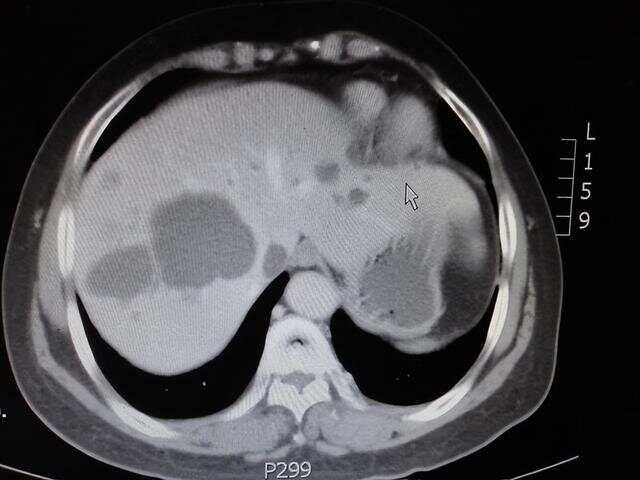

而肝囊肿呢,多是痰瘀蕴结而成,主要是因为情志不畅导致的,可能是经常发脾气,或者多思忧郁,这都会造成肝郁气滞,而气机运行不畅啊,血液就会瘀滞了,日久也就形成了血瘀,这血瘀呢,是肝囊肿的主要成分,而郁金活血行气的功效,不仅能化开血瘀,加速血液流通,防止囊肿进一步长大、增多,同时还能打破已经存在的囊肿,既有治标的功效,又有治本的作用。

如果肝郁日久,横犯到脾胃,导致脾虚生痰湿,这痰湿的性质黏腻,很容易堵塞在肝脏和血瘀包裹成一团,导致囊肿变得更加顽固难祛除,而郁金行气解郁的作用,可以推动痰湿行走,防止瘀堵,正如中医常说的“气顺痰自消”,这可以避免囊肿变大变顽固。